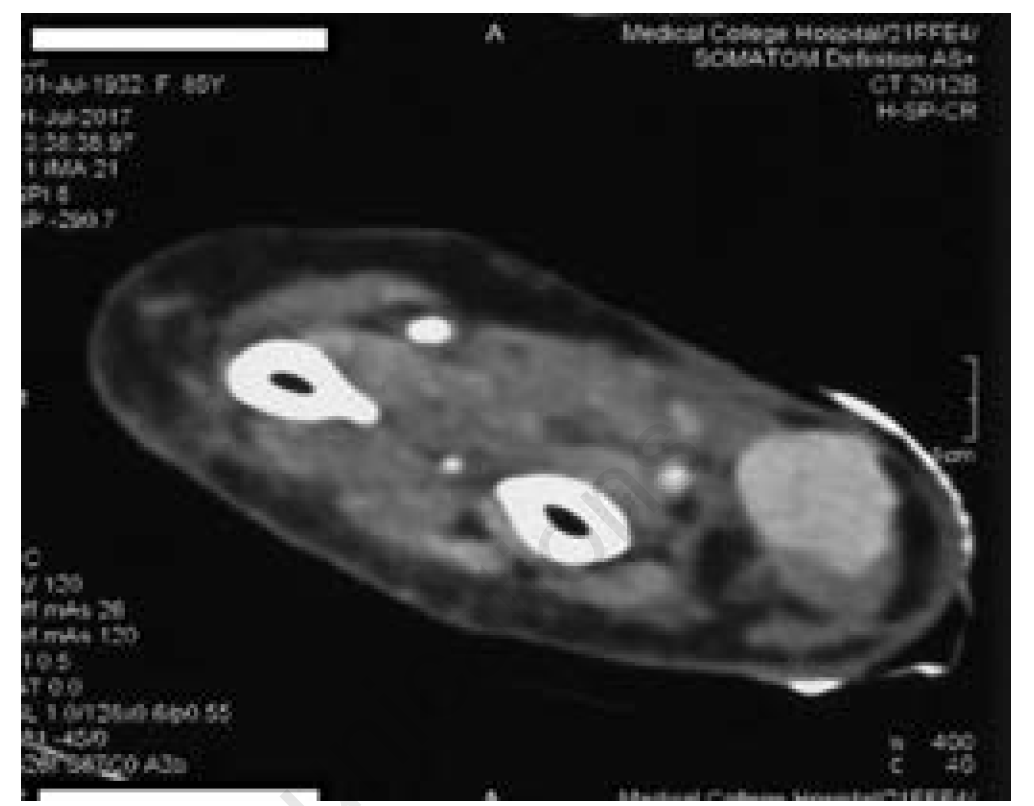

Doppler of the right radial artery revealed a 1.4 x 4 cm mass from the distal end of the right radial artery with a typical yin yang pattern of color flow suggestive of a radial pseudoaneurysm. CT angiogram of the radial artery showed that the right radial artery was normal in course and caliber. Contrast filled an out-pouching measuring 1.7 x 2 x 3.3 cm seen about 5 cm proximal to the radial styloid process. The neck of the pseudoaneurysm measured 2.3 mm. No extravasation or filling defects or thrombus were noted (as per the radiologist). In Figure 3, a thrombus can be seen outside the pseudoaneurysm. The right superficial and deep palmar arches were normal, as were the right ulnar and right brachial arteries.